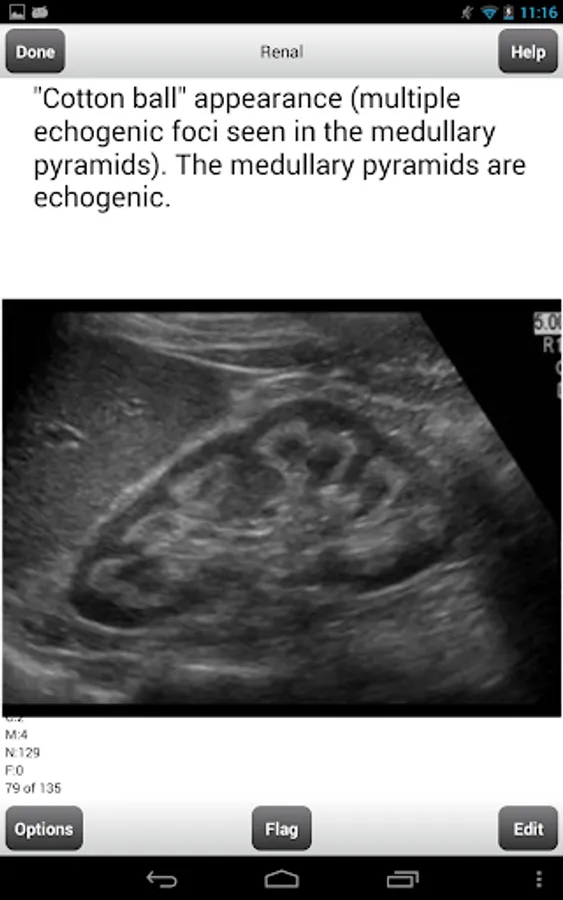

Renal - 135 flashcards